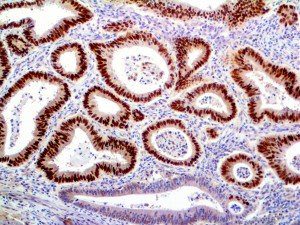

It is the ICU physician who is most likely to witness one of the deadliest manifestations of the abnormal immunological response, the cytokine storm syndrome (CSS). This response is also referred to by some as the cytokine release syndrome (CRS). CSS is characterized by continuous activation and expansion of macrophage and lymphocyte populations, which secrete large amounts of cytokines, causing the cytokine storm. This massive cytokine release is akin to hemophagocytic lymphohistiocytosis (HLH) disease, a syndrome characterized by initial unchecked and persistent activation of cytotoxic T lymphocytes and NK cells.

Clinical and laboratory manifestations of HLH include fever, enlarged liver and/or spleen, neurologic dysfunction, coagulopathy, liver dysfunction, cytopenias (i.e., low levels of erythrocytes, leukocytes, and/or platelets), hypertriglyceridemia, hyperferritinemia, hemophagocytosis, and eventually diminished NK cell activity as the immune system becomes progressively paralyzed. HLH can be familial (primary HLH) or secondary to another disease process (sHLH), such as rheumatic disease, in which it is referred to as macrophage activation syndrome (MAS, characterized by elevated ferritin).